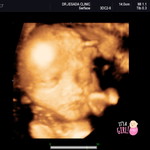

ครบ19 w หมอนัดอัลซาวน์แล้วเจอซีสต์ที่รกค่ะ ขนาด 1.3 CM. หมอนัดอีกเดืแนหน้าว่าซีสต์จะโตขึ้นไหม .. ตอนนี้กลุ้มใจมาก กลัวไปหมด กังวลมากค่ะ ใครพอมีประสบการณ์ หรือคนใกล้ตัวเจอ แบบนี้ บ้างค่ะ ขอความรู้หน่อยคะ เครียดมากก